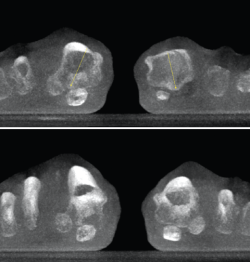

Figura 4. Estudio de la articulación subtalar bilateral.

- Patología y deformidad subtalares. Estudio de la configuración subtalar y artropatía de la misma (Figura 4).

Figura 5. Artropatía de la columna medial en paciente operada de artrodesis astragaloescafoidea.

Figura 6. Artropatía de la columna medial.

- Inestabilidad de la columna medial o inestabilidad tarsometatarsiana. Valoración y estudio de la columna medial en carga (Figuras 5 y 6).